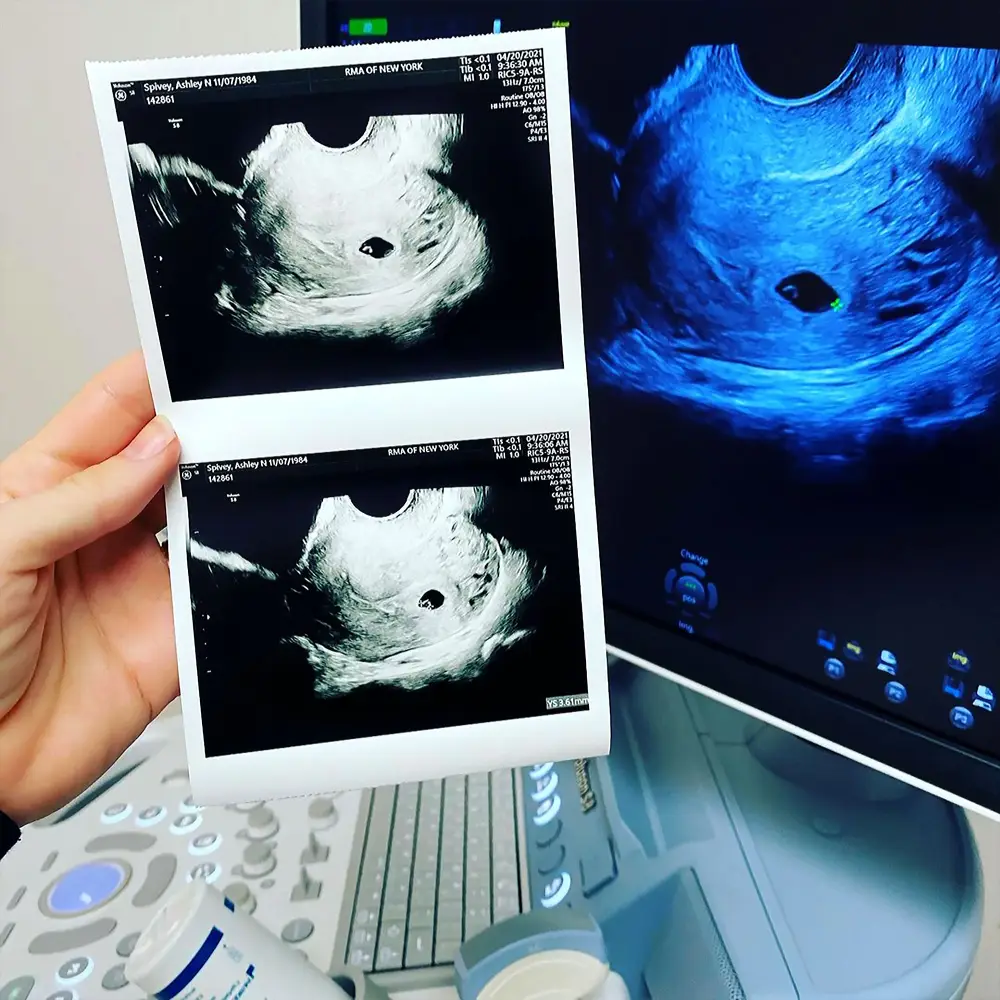

Baby bliss! Ashley Spivey revealed that she is six weeks pregnant, five months after suffering a miscarriage.

“Plot twist🤰🏼,” Spivey, 36, wrote via Instagram on Wednesday, April 21, alongside a photo of her ultrasound. “As y’all all know, I just went through the IVF process and we had decided to freeze the embryos to give my body a little more time to rest. We planned on transferring in May but I should have known, as with many parts of my life — if you want to make God laugh, tell him your plans.”

The season 15 Bachelor alum noted that it’s “still very early” — just six weeks and six days into her pregnancy — but she wanted to share the happy news.